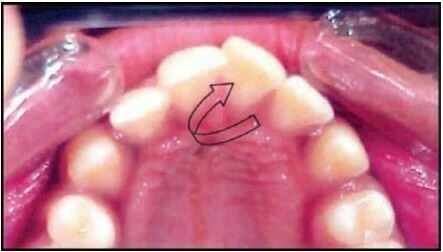

1.7 RĂNG XOAY

Đây là tình trạng những răng di chuyển xung quanh trục dọc của nó. Có hai kiểu xoay răng:

Xa trong hoặc gần ngoài

Mặt xa của răng nghiêng vào trong, hay nói cách khác mặt gần của thân răng nằm về phía ngoài so với mặt xa của nó.